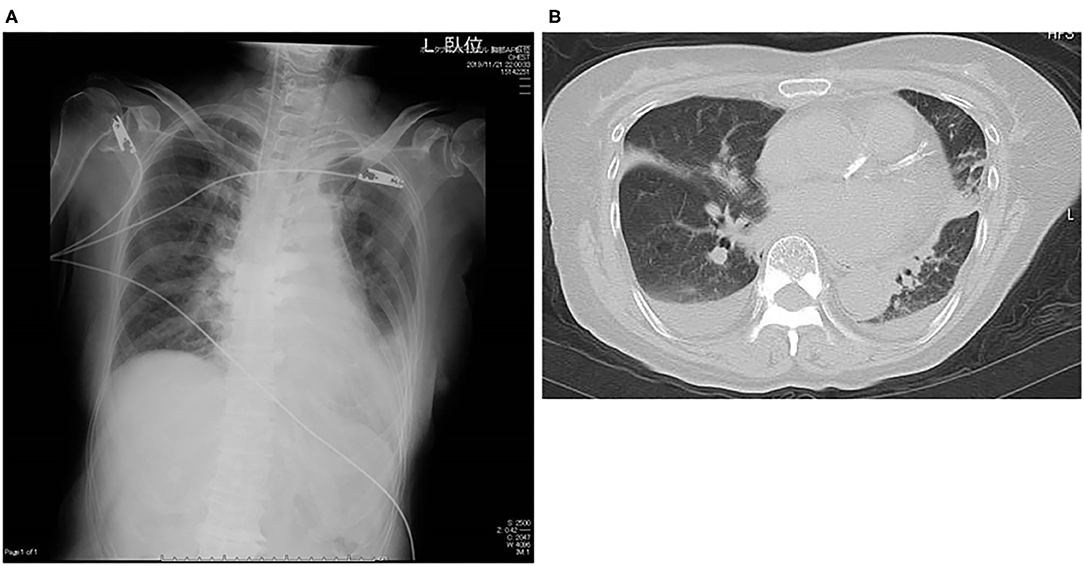

Laboratory examination on admission included serum chemistry showing total protein 5.8 g/dL, albumin 3.2 g/dL, CK 215 IU/L (CK-MB 19 IU/L), CRP 0.3 mg/dL, BNP 348.5 pg/mL, troponin T (TnT) 0.01 ng/mL, Na 139 mEq/L, Ca 9.2 mEq/L, and K 2.1 mEq/L. Hematology indicated mild anemia (hemoglobin of 10.3 g/dl) associated with white blood cell and platelet counts of 8,500/μL and 25.1 × 104/μL, respectively. ECG showed sinus rhythm, left axis deviation, flat or inverted T waves observed in II, III, aVF, V5−6, and QT prolongation (grade I), i.e., QT interval corrected by heart rate (QTc = QT/RR0.5) was 455 ms (Figure 1A). Chest X-ray showed cardiomegaly and chest computed tomography demonstrated bilateral pleural effusion (Figures 2A,B). Ejection fraction was 64% on echocardiogram. Chemotherapeutic regimen including osimertinib, oral itraconazole and herbal medicine (TJ-48) were discontinued, and supplementation of potassium was started. Considering possible ischemic T wave changes (Figure 1A), coronary angiogram was performed. Stenotic lesion (99%) was found in the right coronary artery (segment 1) and collateral circulation supplied from left anterior descending artery was observed (Figures 3A,B). Percutaneous coronary intervention (PCI) was completed successfully by stent implantation at the culprit lesion (Figures 3C,D). QTc interval after the successful PCI and restoration of hypokalemia (K of 4.0 mEq/L) was 432 ms (Figure 1B), and she discharged on foot 33 days after admission without any neurological sequelae of cardiac arrest. Administration of osimertinib (40 mg once daily) was resumed in the hospital where she had been started chemotherapy under the monitoring of ECG and serum potassium concentration while coadministration of itraconazole and herbal drug was interrupted.

FIGURE 2

www.frontiersin.org

Figure 2. Chest X-ray on admission (A) and chest computed tomography during hospitalization (B).